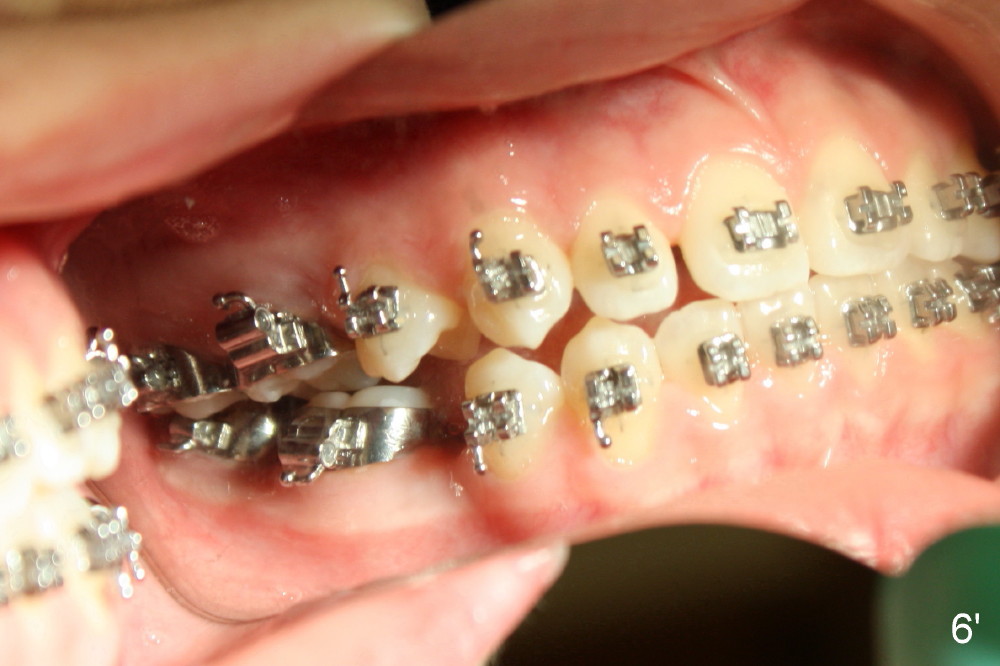

A 13-year-old Asian girl seeks orthodontic treatment for crowding. The lower 2nd bicuspids are congenitally missing (Fig.1,8), whereas the upper right one rotates 180° and the upper left is partially impacted (Fig. 1, 7). The lip muscles strain when the lips close (Fig.3). Orthodontic treatment started with extraction of four affected teeth (#4,13, K and T) 6 months ago. .018' niti wires are being used. Dental midlines do not coincide preop and intraop (Fig.4,4'). Pre-op front view shows that the upper dental midline coincides with the facial one (Fig.1'). There is Class I canine and molar relationship on the right (Fig.5,5',9,9'); open bite on the left (Fig.6,6',10,10').

Update: The left open bite was closed less than one month by wearing elastics between upper and lower teeth (Fig. 6'''). The occlusal plane and midline improve (Fig.4''). Wires have gradually changed to .016x.016, .016x.022 and now .018x.025 with power chains. All the spaces are closed except the one in LR (Fig.7''-10''). What I cannot accomplish is to fix meisal (Fig.5'' (white line), 9'') and lingual (Fig.8'' arrows) inclination of LR molars, although elastic is instructed to be placed between UR7 buccal and LR7 lingual. The rectangular wires could be twisted to fix lingual inclination. Which should be done first: LR space or LR molar inclination? Click each figure for magnification.